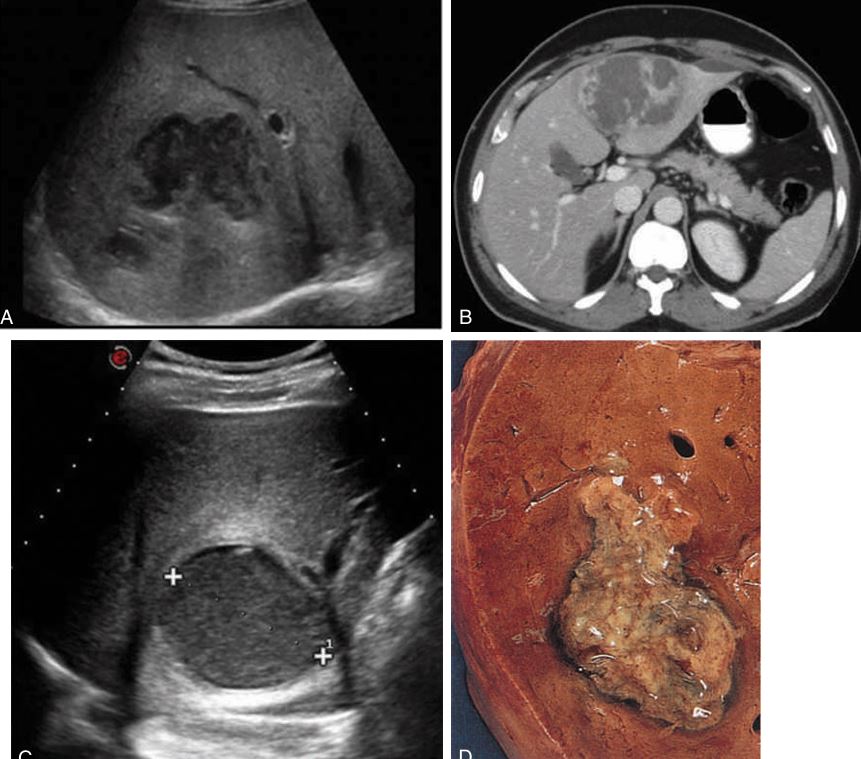

Hepatic adenoma. This lesion is usually hyperechoic with a central hypoechoic area caused by hemorrhage.

The echogenicity of a hepatic adenoma may be hyperechoic, hypoechoic, isoechoic, or mixed. This lesion is usually hyperechoic with a central hypoechoic area caused by hemorrhage. Echogenicity examples: (A) hypoechoic, (B) hyperechoic with hypoechoic central hemorrhage, (C) computed tomographic image of adenoma, (D) hyperechoic, (E) mixed, and (F) hyperechoic with central hemorrhage.

ORAL CONTRACEPTIVES